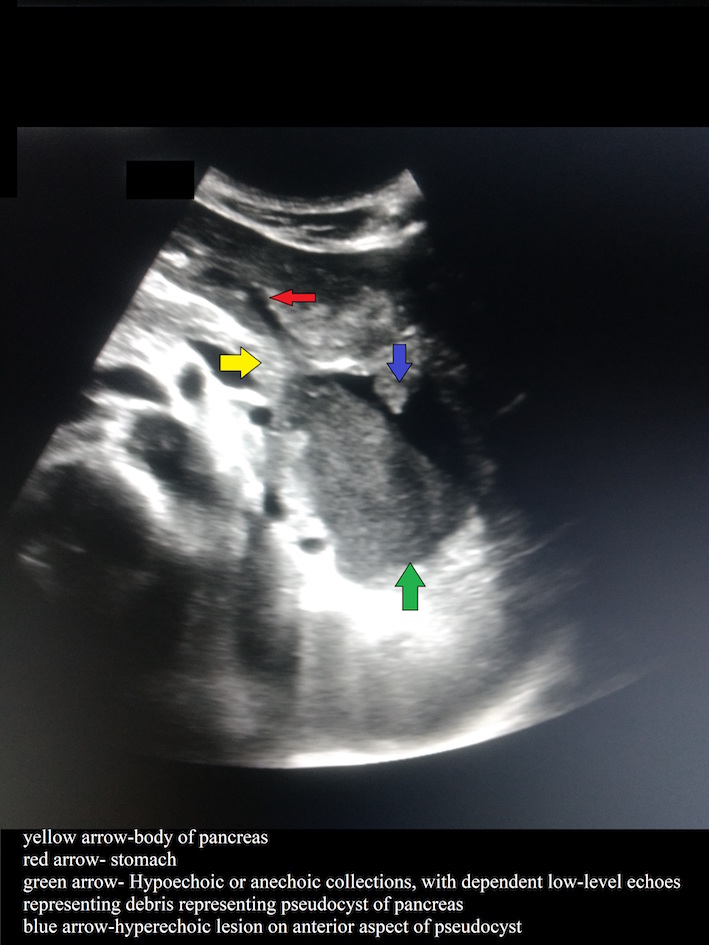

A well-defined oval cyst isseen abutting the pancreatic body and tail, suggestive of a pancreatic pseudocyst. The pancreatic duct is minimally prominent. Thecyst is seen anteriorly abutting the stomach wall with resultant diffuse oedematousthickening of the walls of the stomach.A few ill-defined hyperdensitiesare seen within the cyst, suggestive of chronic hemorrhages/ sludge •Atiny nodular well-defined intensely enhancing lesion is seen along the cyst wall anteriorly on arterialphase representing peseudoaneurysm.

- Pancreatic pseudocysts are common sequelae of acute or chronic pancreatitis and represent one of the most common cystic lesions of the pancreas.

- Pseudocysts appear as well-circumscribed, usually round or oval intra- or peripancreatic fluid collections that are usually surrounded by a well-defined wall. They may or may not have communication with the pancreatic duct.